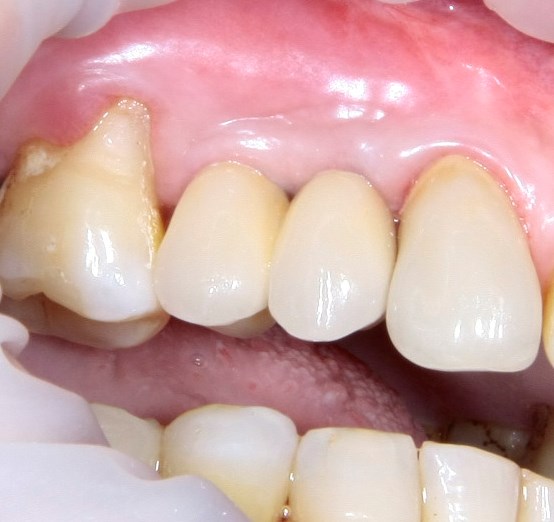

Опыт применения коллагеновой матрицы Mucograft в клинической практике.